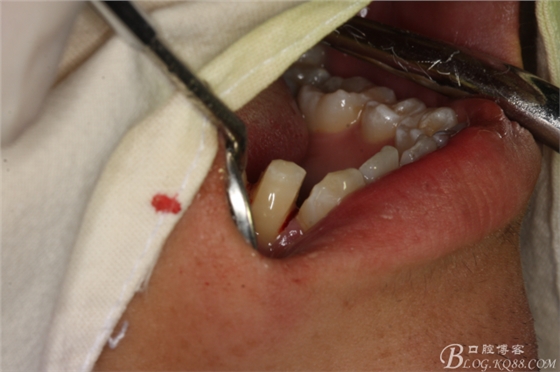

圖11.牙挺分開(kāi)47牙冠

圖12.挺出47頰側(cè)牙冠

圖13.高速拔牙手機(jī)離斷舌側(cè)牙冠

圖14.挺出47舌側(cè)部分牙冠